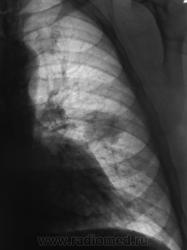

Начало 2008 года. При расшифровке флюорограмм, пациента "взяли на контроль", заподозрили периферический рак левого лёгкого (по "прямой" флюорограмме). Вроде-бы все правильно и логично?

Но мы, пациента дообследовали, рентгенография и томография (аналоговая), высказали мнение о наличии "опухолевого роста" и рекомендовали консультацию онколога, и пациент "поехал" туда, куда послали. Снимков (тех первых) предоставить не могу, остались там, куда "послали". Выписка "рекомендовала" понаблюдать....

В апреле 2009 года пациент пришел "для динамического наблюдения" - серия 2.

После повторного дообследования (апрель 2009 г) - 2 серия изображений, мы были твердо уверены, что пациент взят на учет..., но не тут-то было. В пятницу рентгенолаборант флюорографа попросил подойти и "глянуть снимок"...

Оказывается "данный" пациент направлен для прохождения профилактической флюорографии..., так как надо было поменять водительские права...?

2. Конечно, мы на свой страх и риск, произвели дообследование, согласно стандарту. Итог дообследования представлен в серии 3.